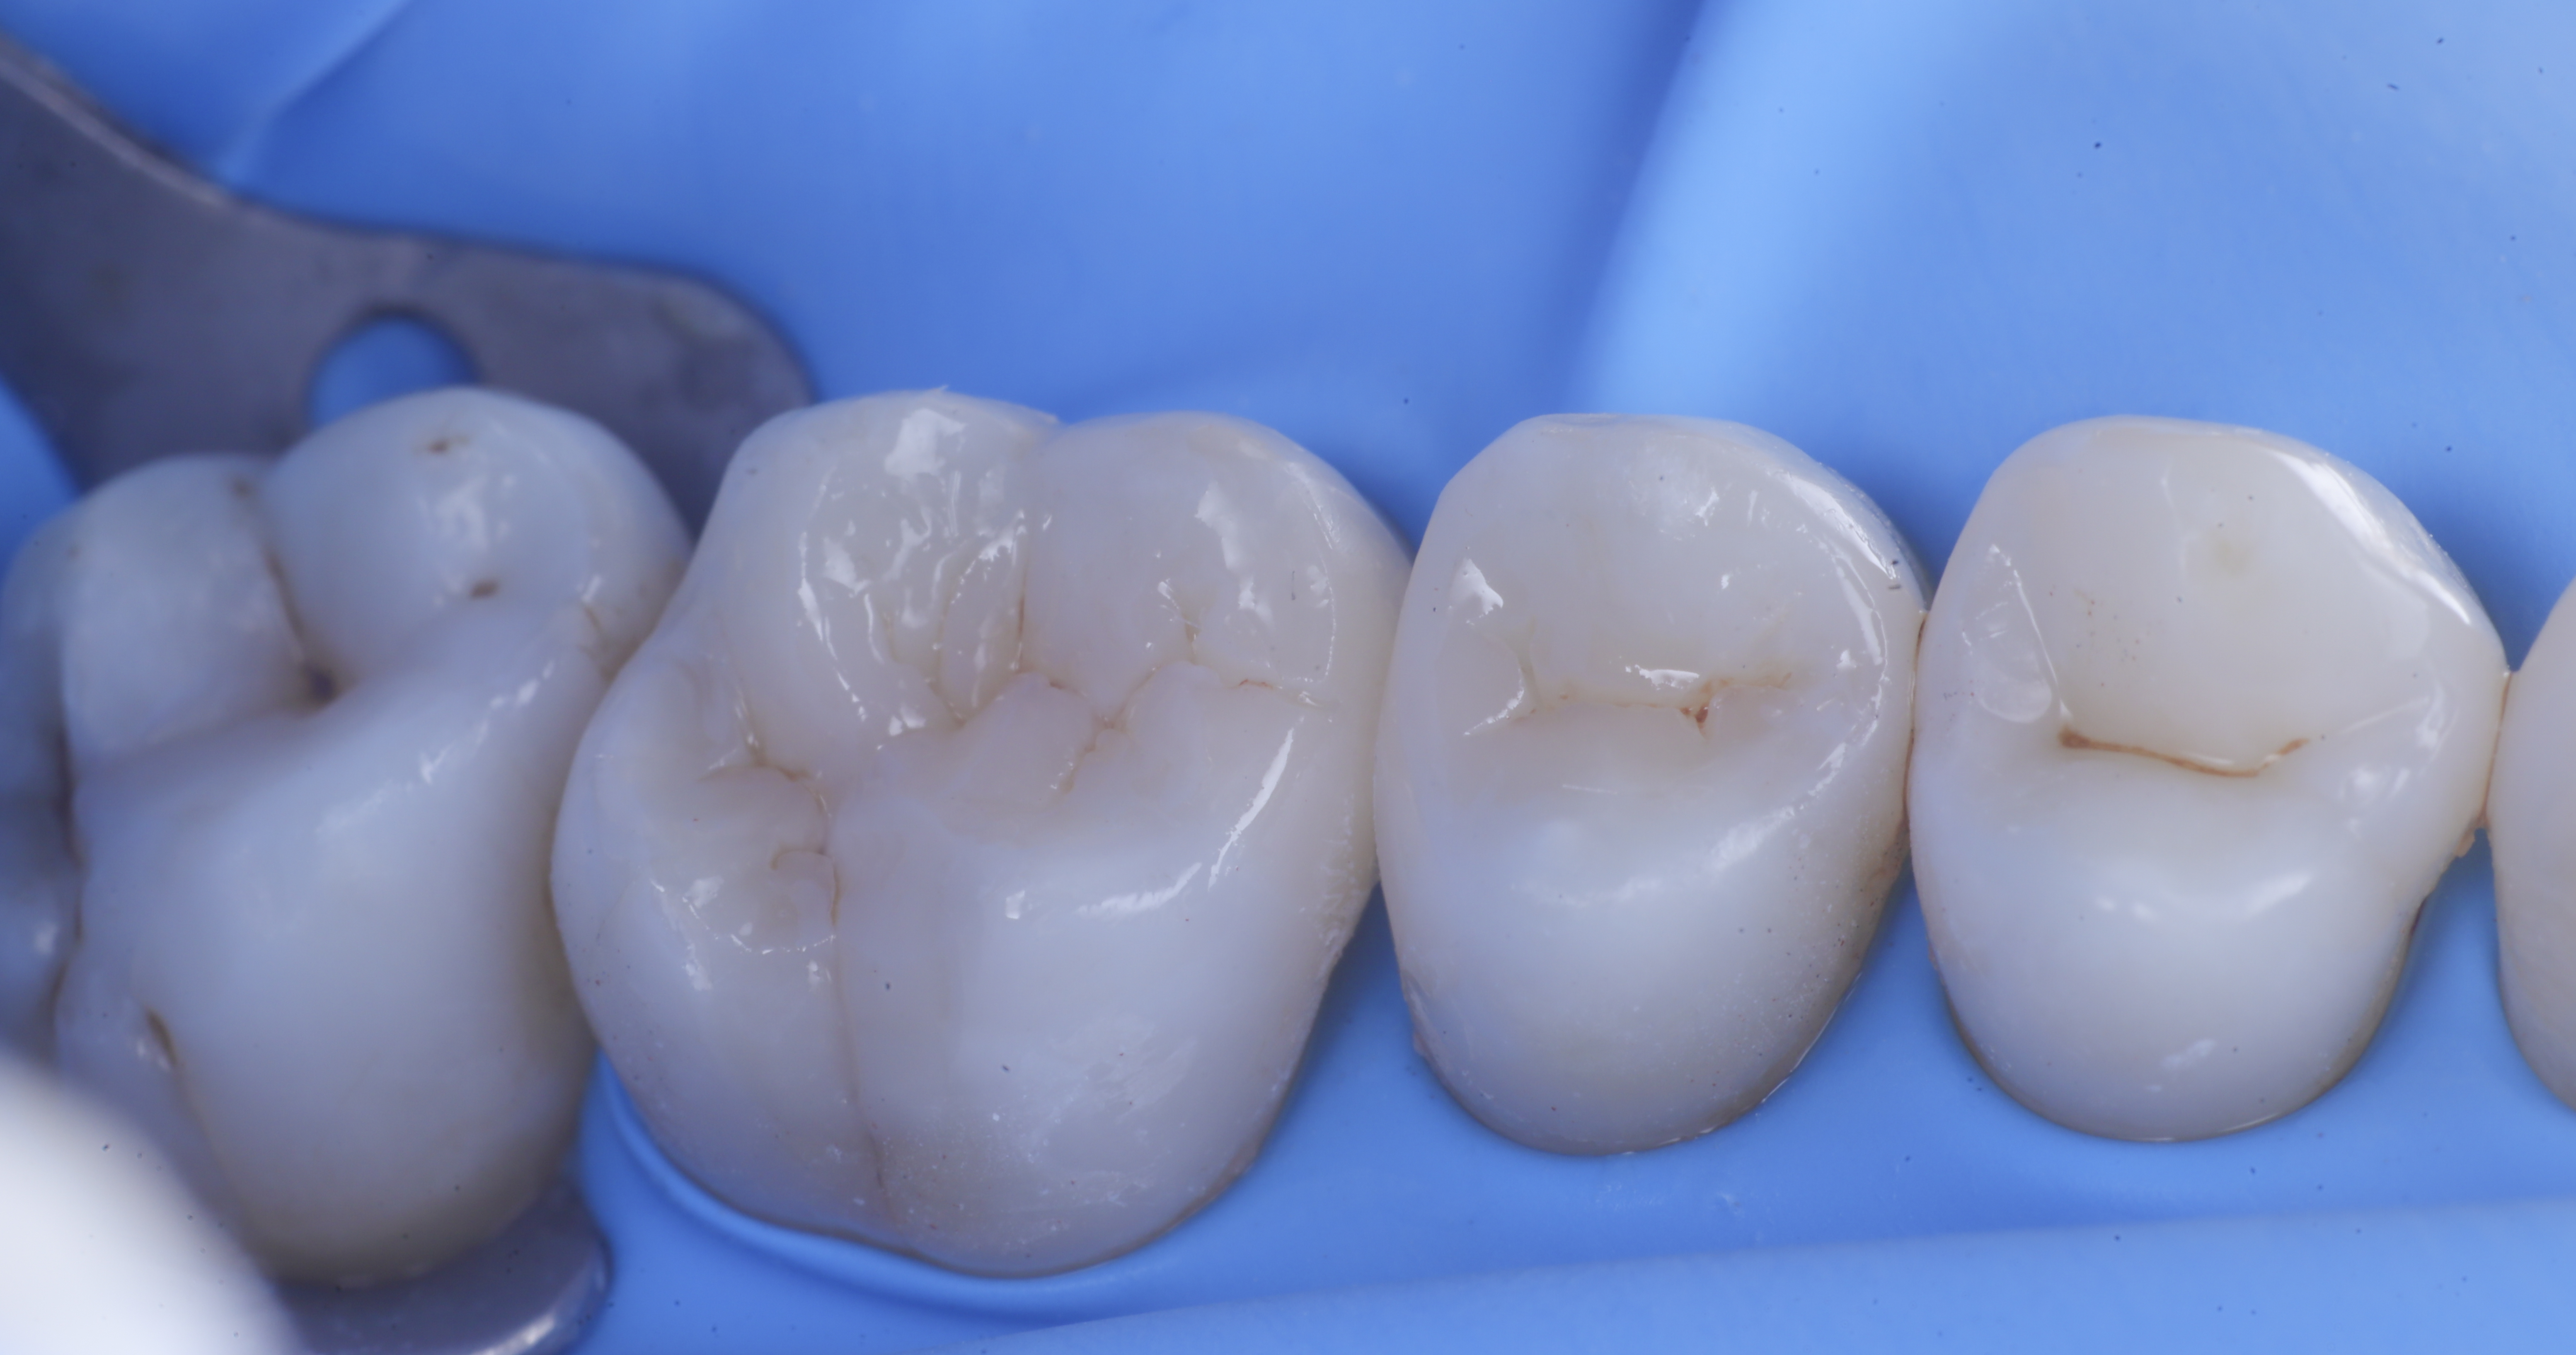

foto 8 Modellazione ed aspetto occlusale

foto 9 Modellazione ed aspetto vestibolare

foto 10 Modellazione ed aspetto palatino

foto 11 Restauri ultimati sotto controllo occlusale

Trasformate le cavita da II classi a I classi si procede con la classica modellazione cuspide per cuspide, sfruttando le caratteristiche meccaniche e anche estetiche dei materiali compositi bulk.